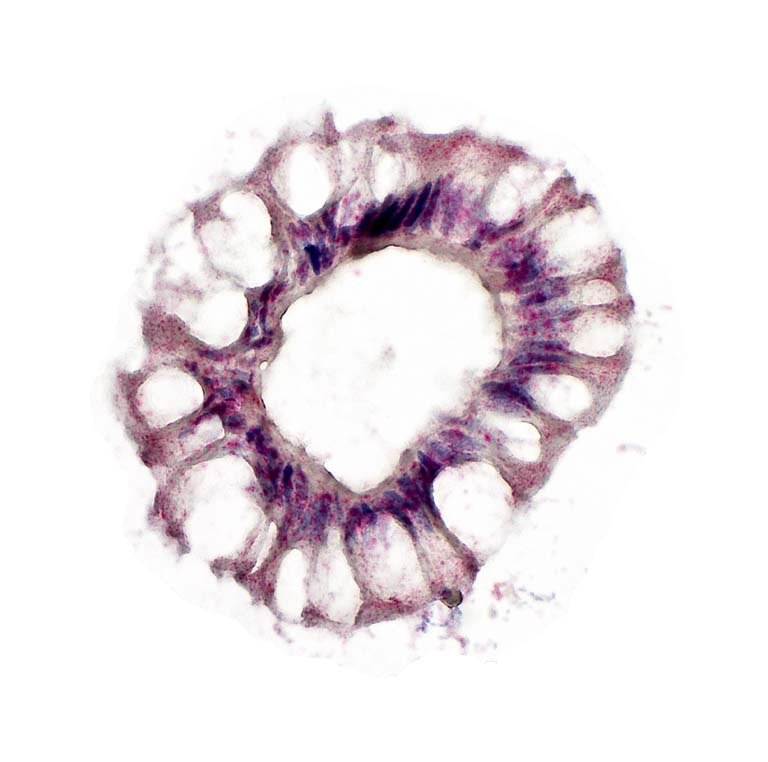

This is staining of COVID-19 (SARS CoV-2 virus) in situ hybridization directly infecting a human colon crypt. This is evidence we used to publish our recent findings that COVID-19 can in fact directly infect the cells in our gut leading to gut symptoms as well as a significant increase in mortality. The red dots are the viral mRNA.